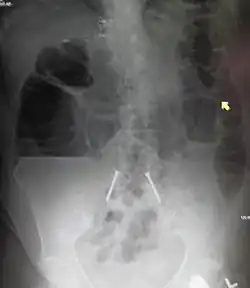

| Upright abdominal X-ray demonstrating a small bowel obstruction. Note multiple air fluid levels. | |